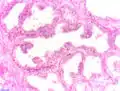

Adénocarcinome prostatique

Adénocarcinome ; tissus indifférenciés

Invasion périneurale par un adénocarcinome prostatique. HE, x400